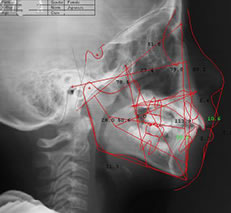

セファロ

セファロ」は、レントゲンの一種です。一般的なレントゲンでは歯全体や上下のあごを中心に撮影しますが、セファロ撮影では頭部全体を正面と横から詳細に撮影します。この手法により、歯の動き方や実際の動きを数値的に把握することが可能になります。